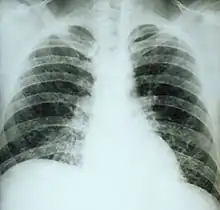

If symptoms of histoplasmosis infection occur, they start within 3 to 17 days after exposure; the typical time is 12–14 days. Most affected individuals have clinically silent manifestations and show no apparent ill effects. The acute phase of histoplasmosis is characterized by nonspecific respiratory symptoms, often cough or flu-like. Chest X-ray findings are normal in 40–70% of cases.[8] Chronic histoplasmosis cases can resemble tuberculosis;[9][10] disseminated histoplasmosis affects multiple organ systems and is fatal unless treated.[11]